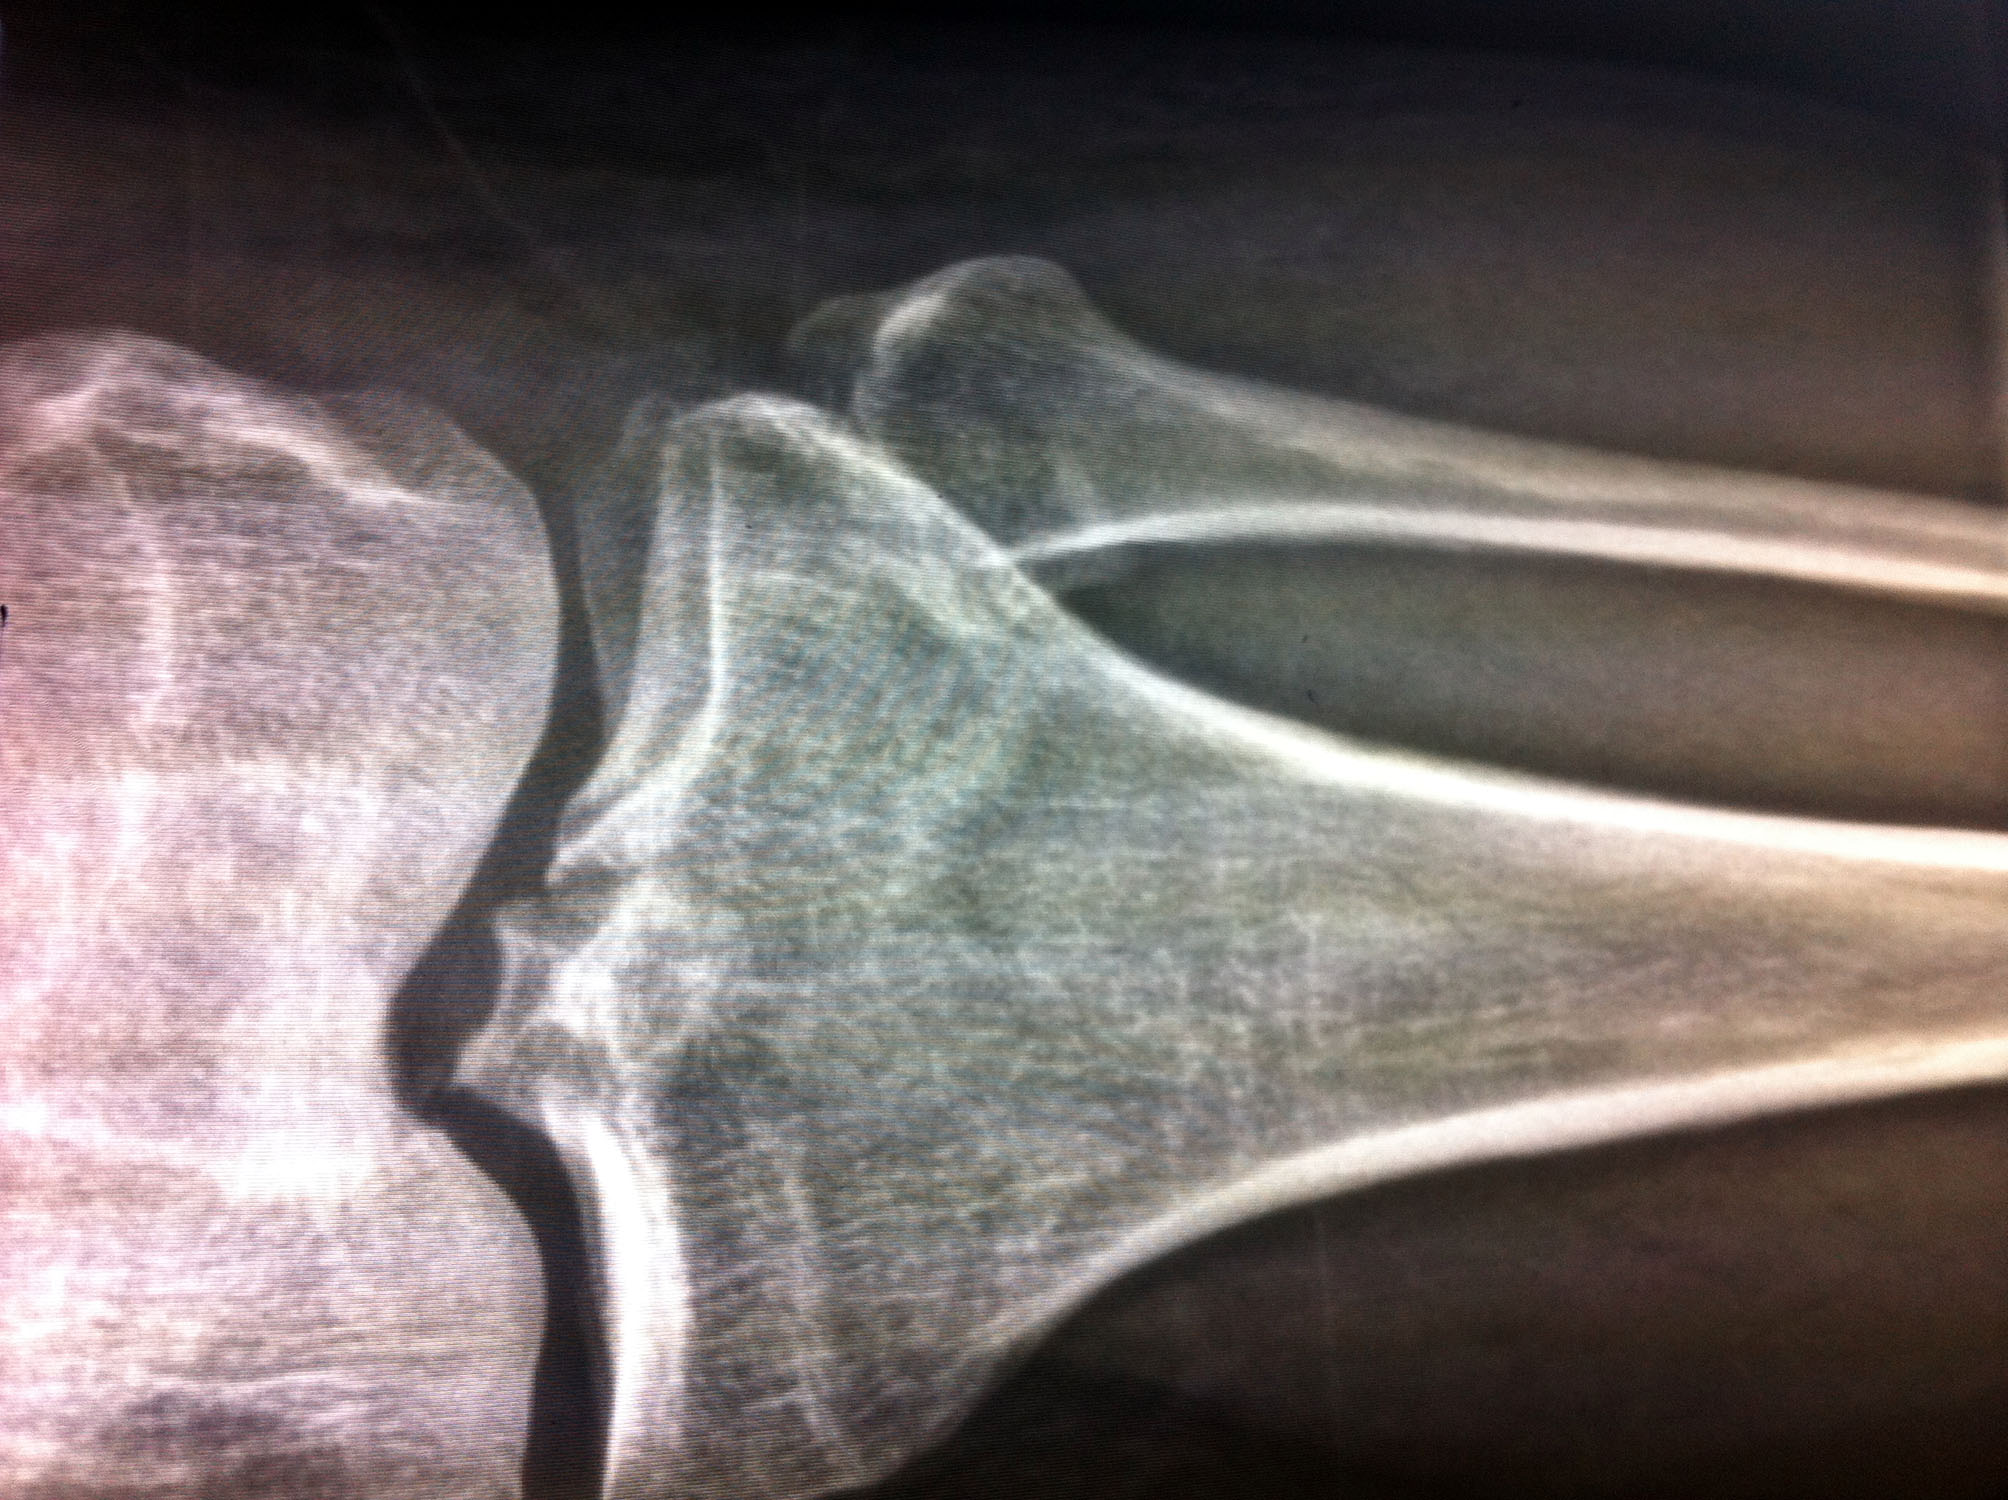

【明慧网二零一四年十一月二十一日】(明慧网通讯员山东报道)二零一四年十月二十五日下午三点,青岛市610(专门迫害法轮功的非法组织)、李沧区610、李沧公安分局和李村派出所警察,绑架、抢劫法轮功学员牛西雹、张定钢、王德铜、李洪升。其中,牛西雹(男、五十二岁)被非法关押在普东看守所至今,张定钢左腿被打骨折。

张定钢左腿被打骨折

张定钢,男、四十八岁,十月二十五日下午被绑架期间,左腿被打骨折,不能行走,用于做生意的面包车,两部手机,家中钥匙、现金约一万六千元,被非法劫走,扣留在李村派出所,家人一直在索要,恶警始终不给,分管的警察的电话:0532-6657661

张定钢于十月二十七日晚被取保回家,一直躺在床上不能下地,家中失去了经济来源,钱物被非法扣留,致使他不能得到及时治疗,家中上有九十岁的老人,下有上学的孩子,妻子还得照顾他,给生活造成困难。